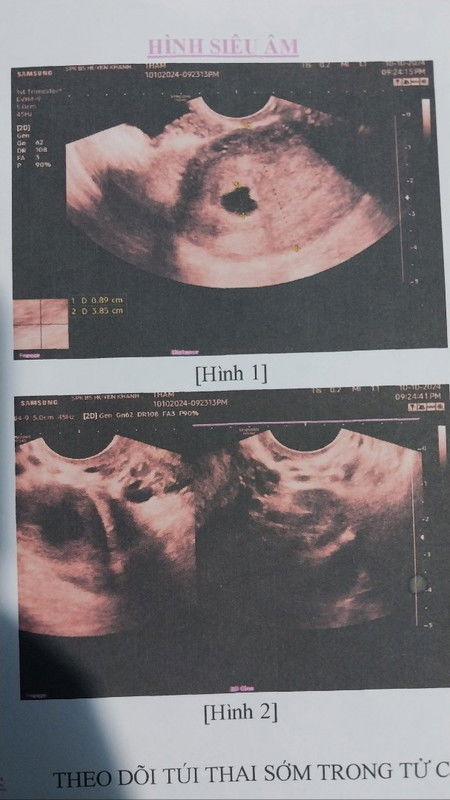

Em k rõ tuần thai, nhưng tính từ ngày kinh gần nhất thì được 5 tuần 2 ngày rồi ạ. Em đi khám thì bác sĩ bảo túi thai bị méo, hình túi thai như này có khả năng thai dị dạng hoặc hỏng, rồi bảo tuần sau tái khám. Thai vẫn nhỏ nên cần theo dõi thêm. Các chị đi trước cho em xin ít chia sẻ với ạ. Giờ em nghỉ ở nhà an dưỡng luôn rồi #Các_Mom_chỉ_bảo_em_với_ạ #mebau 16/11/24: thai lưu cho ra